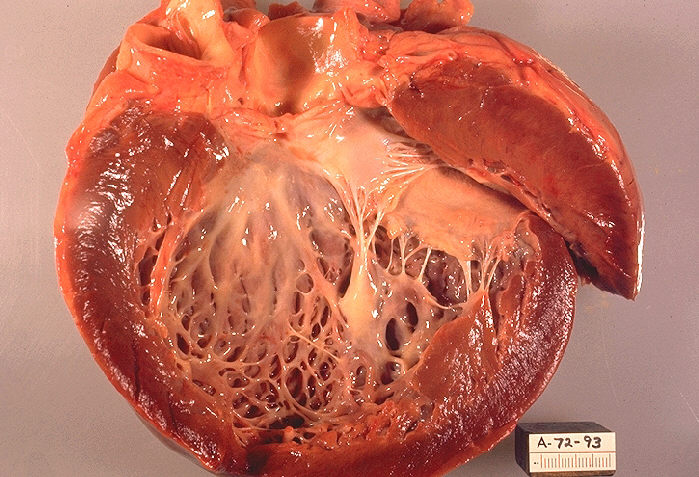

Кардиомиопатия. Это заболевание миокарда, которое нарушает формирование сердечной мышцы. В результате происходит увеличение клеток миоцитов и размера сердца, что пропорционально снижает его функциональную активность. Виды кардиомиопатии могут быть различными: врожденные, токсические, алкогольные и другие.

Инфаркт. Это омертвение участка сердечной мышцы, которое происходит стремительно. Ткани миокарда атрофируются в течение нескольких часов, и значительные площади заменяются рубцовыми структурами. Блокада в таких случаях может варьироваться от нескольких пучков до полной блокировки ножки.